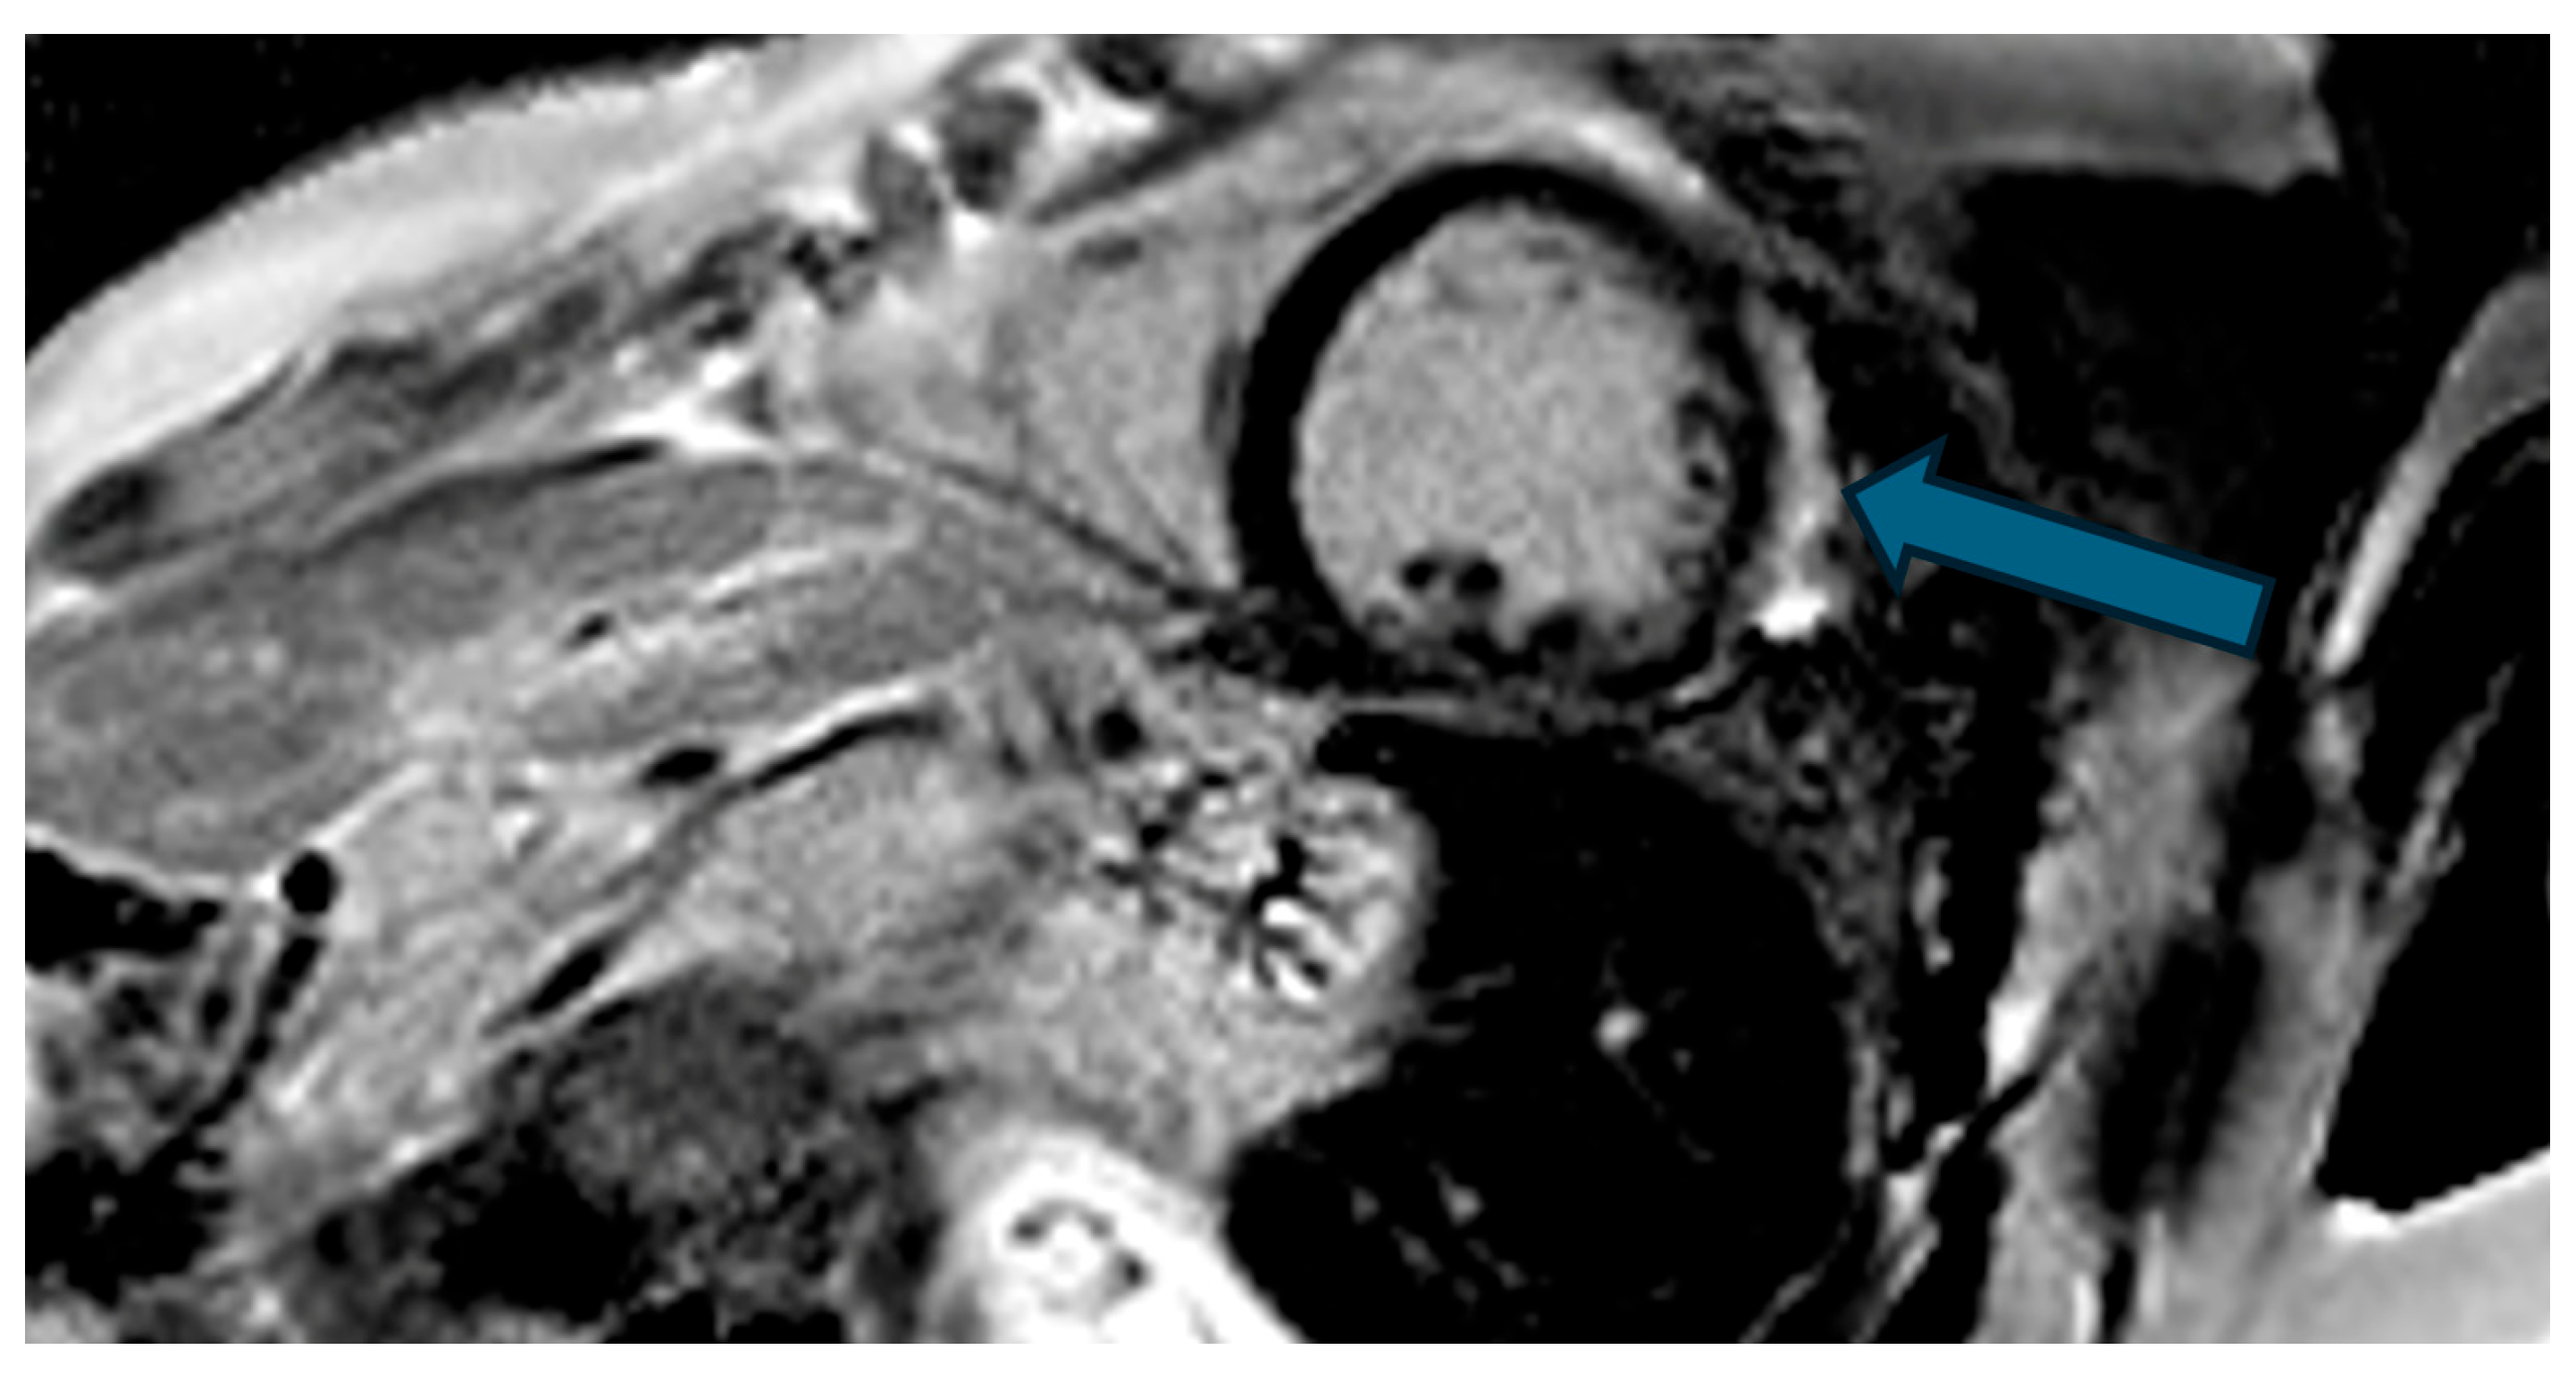

Figure 5.

Cardiac magnetic resonance (CMR), phase-sensitive inversion recovery (PSIR) sequence for late gadolinium enhancement (LGE), three-chamber view. The hyperintensity of the basal lateral wall of the left ventricle (arrow) is shown, compatible with non-ischemic intramyocardial fibrosis.